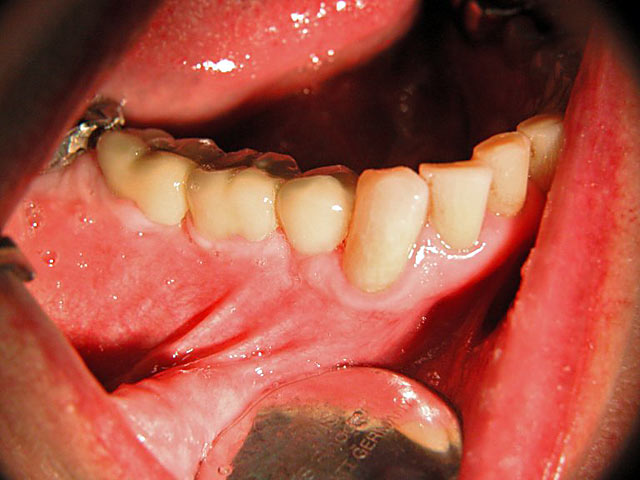

Die folgenden Patientenfälle sollen Ihnen einen Einblick in die Möglichkeiten der modernen Implantation geben.

Implantation – Patientenbeispiel 2: